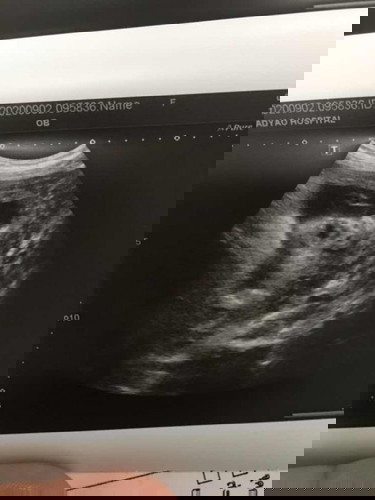

รูปอัลตราซาวด์ล่าสุด

จากที่เคยโพสไปว่าไม่เคยได้รูปอัลตราซาวด์ แล้วได้คำแนะนำจากแม่หลายๆบ้านตอนนี้มี1รูปแล้วจ้า🥰🥰 คุณพ่อดีใจมากเลยค่ะ เหมือนพ่อเดะเลย วันนี้เลยอยากขอดูรูปถ่ายอัลตราซาวด์แม่ๆทีมคลอดเดือนนี้หน่อยจ้า😍😍